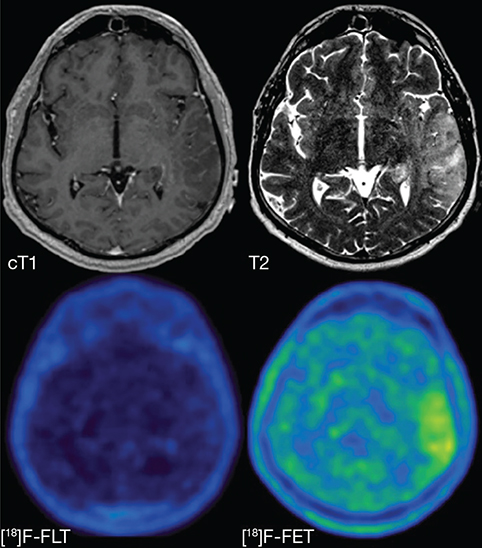

Fig 6

Figure 6. T1-weighted post-contrast (cT1), T2-weighted (T2), 18F-FLT PET ([18]F-FLT) and 18F-FET ([18]F-FET) images of a patient with a non-enhancing glioblastoma, WHO grade IV. The lesion is hyperintense on the T2-weighted image but does not show contrast enhancement. Increased uptake in the T2-hyperintense region can clearly be seen on the 18F-FET PET image, but there is no uptake visible on the 18F-FLT PET image, illustrating the drawback of PET agents that cannot easily cross the BBB. This figure is reproduced – with new figure legend appropriate for current article – from Nowosielski et al. (2014), Figure 1, under the terms of the Creative Commons Attribution 4.0 International (CC BY) License (http://creativecommons.org/licenses/by/4.0) (107).